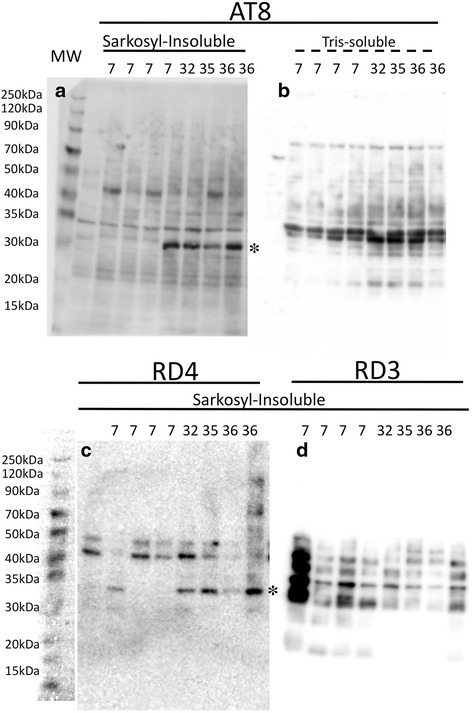

To characterize age-associated changes in tau protein biochemically, we next separated extracts from frozen temporal lobes of young (7 yo), and old (over 30 yo) monkeys into TBS-soluble and sarkosyl-insoluble fractions and probed for AT8-positive (Fig. 8a) and RD4-positive (Fig. 8c) bands by western blotting. In sarkosyl-insoluble fractions, we identified AT8 or RD4-positive bands between 30 and 35KDa in aged monkeys (asterisks) but not in young controls (7 yo). These bands were not found in TBS-soluble fractions (Fig. 8b), or in sarkosyl-insoluble fractions probed with RD3 antibodies (Fig. 8d). Surprisingly, higher molecular complexes at 50–70 kDa, seen in human brains with tau deposits [ref. 23, ref. 24], were neither detectable in the sarkosyl-insoluble preparations nor in the TBS-soluble preparations. These findings were confirmed in duplicate experiments.

PSP-like tau fragments in aged monkey brains

The sarkosyl-insoluble fraction from aged monkey brains (32–36 yo) contained 30–34 kDa bands positive for AT8 and RD4, not found in young controls (7 yo) (Table 1, Fig. 8). Tau-positive bands in this molecular range have been reported to be specific to PSP, and are distinct from AD [ref. 23, ref. 24]. Curiously, full-length hyperphosphorylated tau (60, 64 and 68 kDa, Fig. 8a, c) was not detected in sarkosyl-insoluble fractions from young or aged monkeys, and it remains to be clarified how these shorter tau fragments are generated. The absence of full-length tau in these fractions may be related to scarcity of neuronal tau (Fig. 7), while solid fibrillary structures in oligodendroglia-like cells (Fig. 6) may correspond to the 30–34 kDa sarkosyl-insoluble fragments. Thus, it is possible that neuronal tau in human brains with PSP consists mainly to full-length tau, while glial tau consists of the 30–34 kDa fragments, although this interpretation remains to be proved.